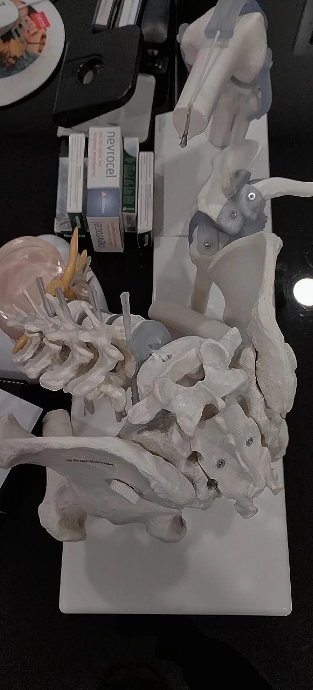

Arthroskopische Gelenkchirurgie

Minimalinvasive Chirurgie für schnelle Genesung

Zu meinen Spezialisierungen zählen arthroskopische Eingriffe am Knie und anderen Gelenken. Bei Meniskus- oder Kreuzbandverletzungen ermöglicht minimalinvasive Technik eine präzise Behandlung über kleinste Schnitte. Das umliegende Gewebe wird geschont, postoperative Beschwerden werden reduziert und die Genesung verläuft deutlich schneller.

Minimalinvasive Endoprothetik (Hüfte & Knie)

Gelenkersatz mit Präzision, Schonung und Langzeitwirkung

Ich führe Hüft- und Knieprothesenoperationen mit minimalinvasiven Techniken durch. Diese schonenden Verfahren reduzieren den Blutverlust, verringern postoperative Schmerzen und verkürzen die Genesungszeit. Hochwertige Implantate sorgen dafür, dass Sie Ihre Beweglichkeit langfristig verbessern und Ihre Lebensqualität steigern können.